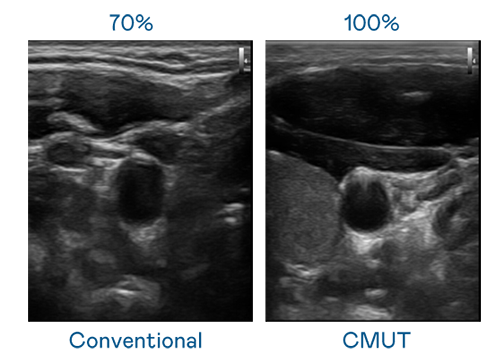

CMUT 技术是一种用电容式微机电元件来产生超音波讯号的技术。与传统 PZT 压电式技术相比,CMUT 频宽增加 30%,更宽频的超音波讯号让影像解析度大幅提升,是实现高影像品质医疗超音波扫描、促进精准医疗发展的关键技术。

超音波影像的解析度高低,首先取决于探头能发出的讯号频宽。环球360 CMUT 可提供高清晰的超音波讯号,提供高频宽、高灵敏度、影像纹理细节更高的超音波影像,协助医护人员缩短影像判读时间及利用精准的医疗影像进行诊断。